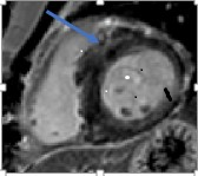

Fibrosis in the basal anteroseptal wall segment and in the apical lateral wall segment, with an estimated fibrosis mass of 17%